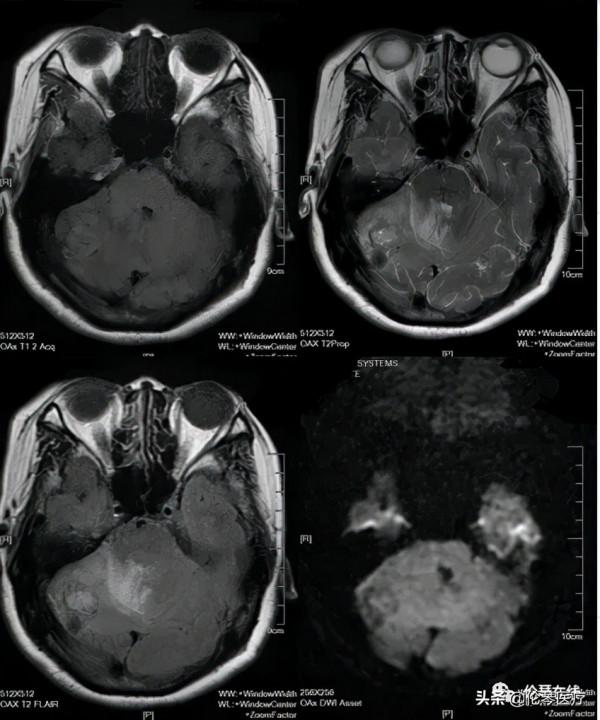

關鍵影象: